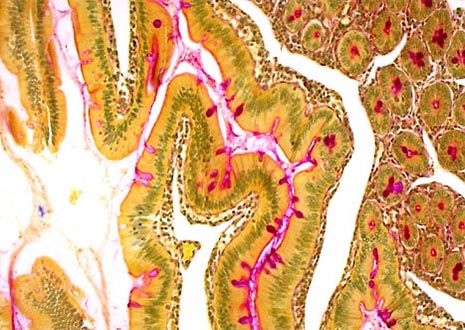

Human Intestinal Tissue

The gut, sometimes referred to as the alimentary canal or the gastrointestinal tract, is approximately nine meters long in the typical human adult. Although metabolism rates differ from person to person, food generally takes 18 to 20 hours to completely pass through the gut.